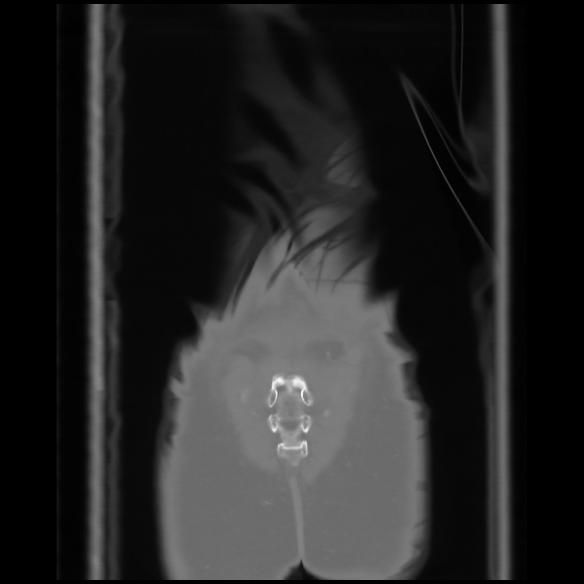

6 CUERPO,CE,Coronal,3.000,CUERPO,Coronal,